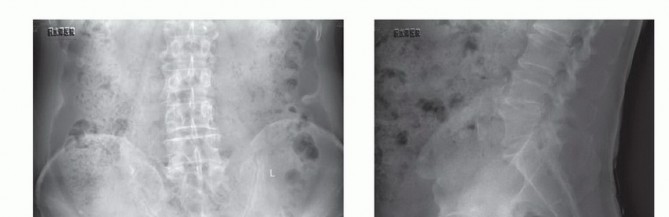

التصوير بالأشعة السينية العادية

قد تكون صور الأشعة السينية العادية غير واضحة في المراحل المبكرة من المرض. ومع ذلك، يمكن أن تساعد في تشخيص بعض الأورام، مثل الورم الحبلي الذي غالبًا ما يقع في الجزء السفلي من العجز، أو الأورام الكبيرة والمحللة تمامًا مثل ورم الخلايا العملاقة أو الكيس العظمي المتمدد في الجزء العلوي من العجز. تُعد الأشعة السينية ضرورية لإعطاء نظرة عامة ومتابعة ما بعد الجراحة.